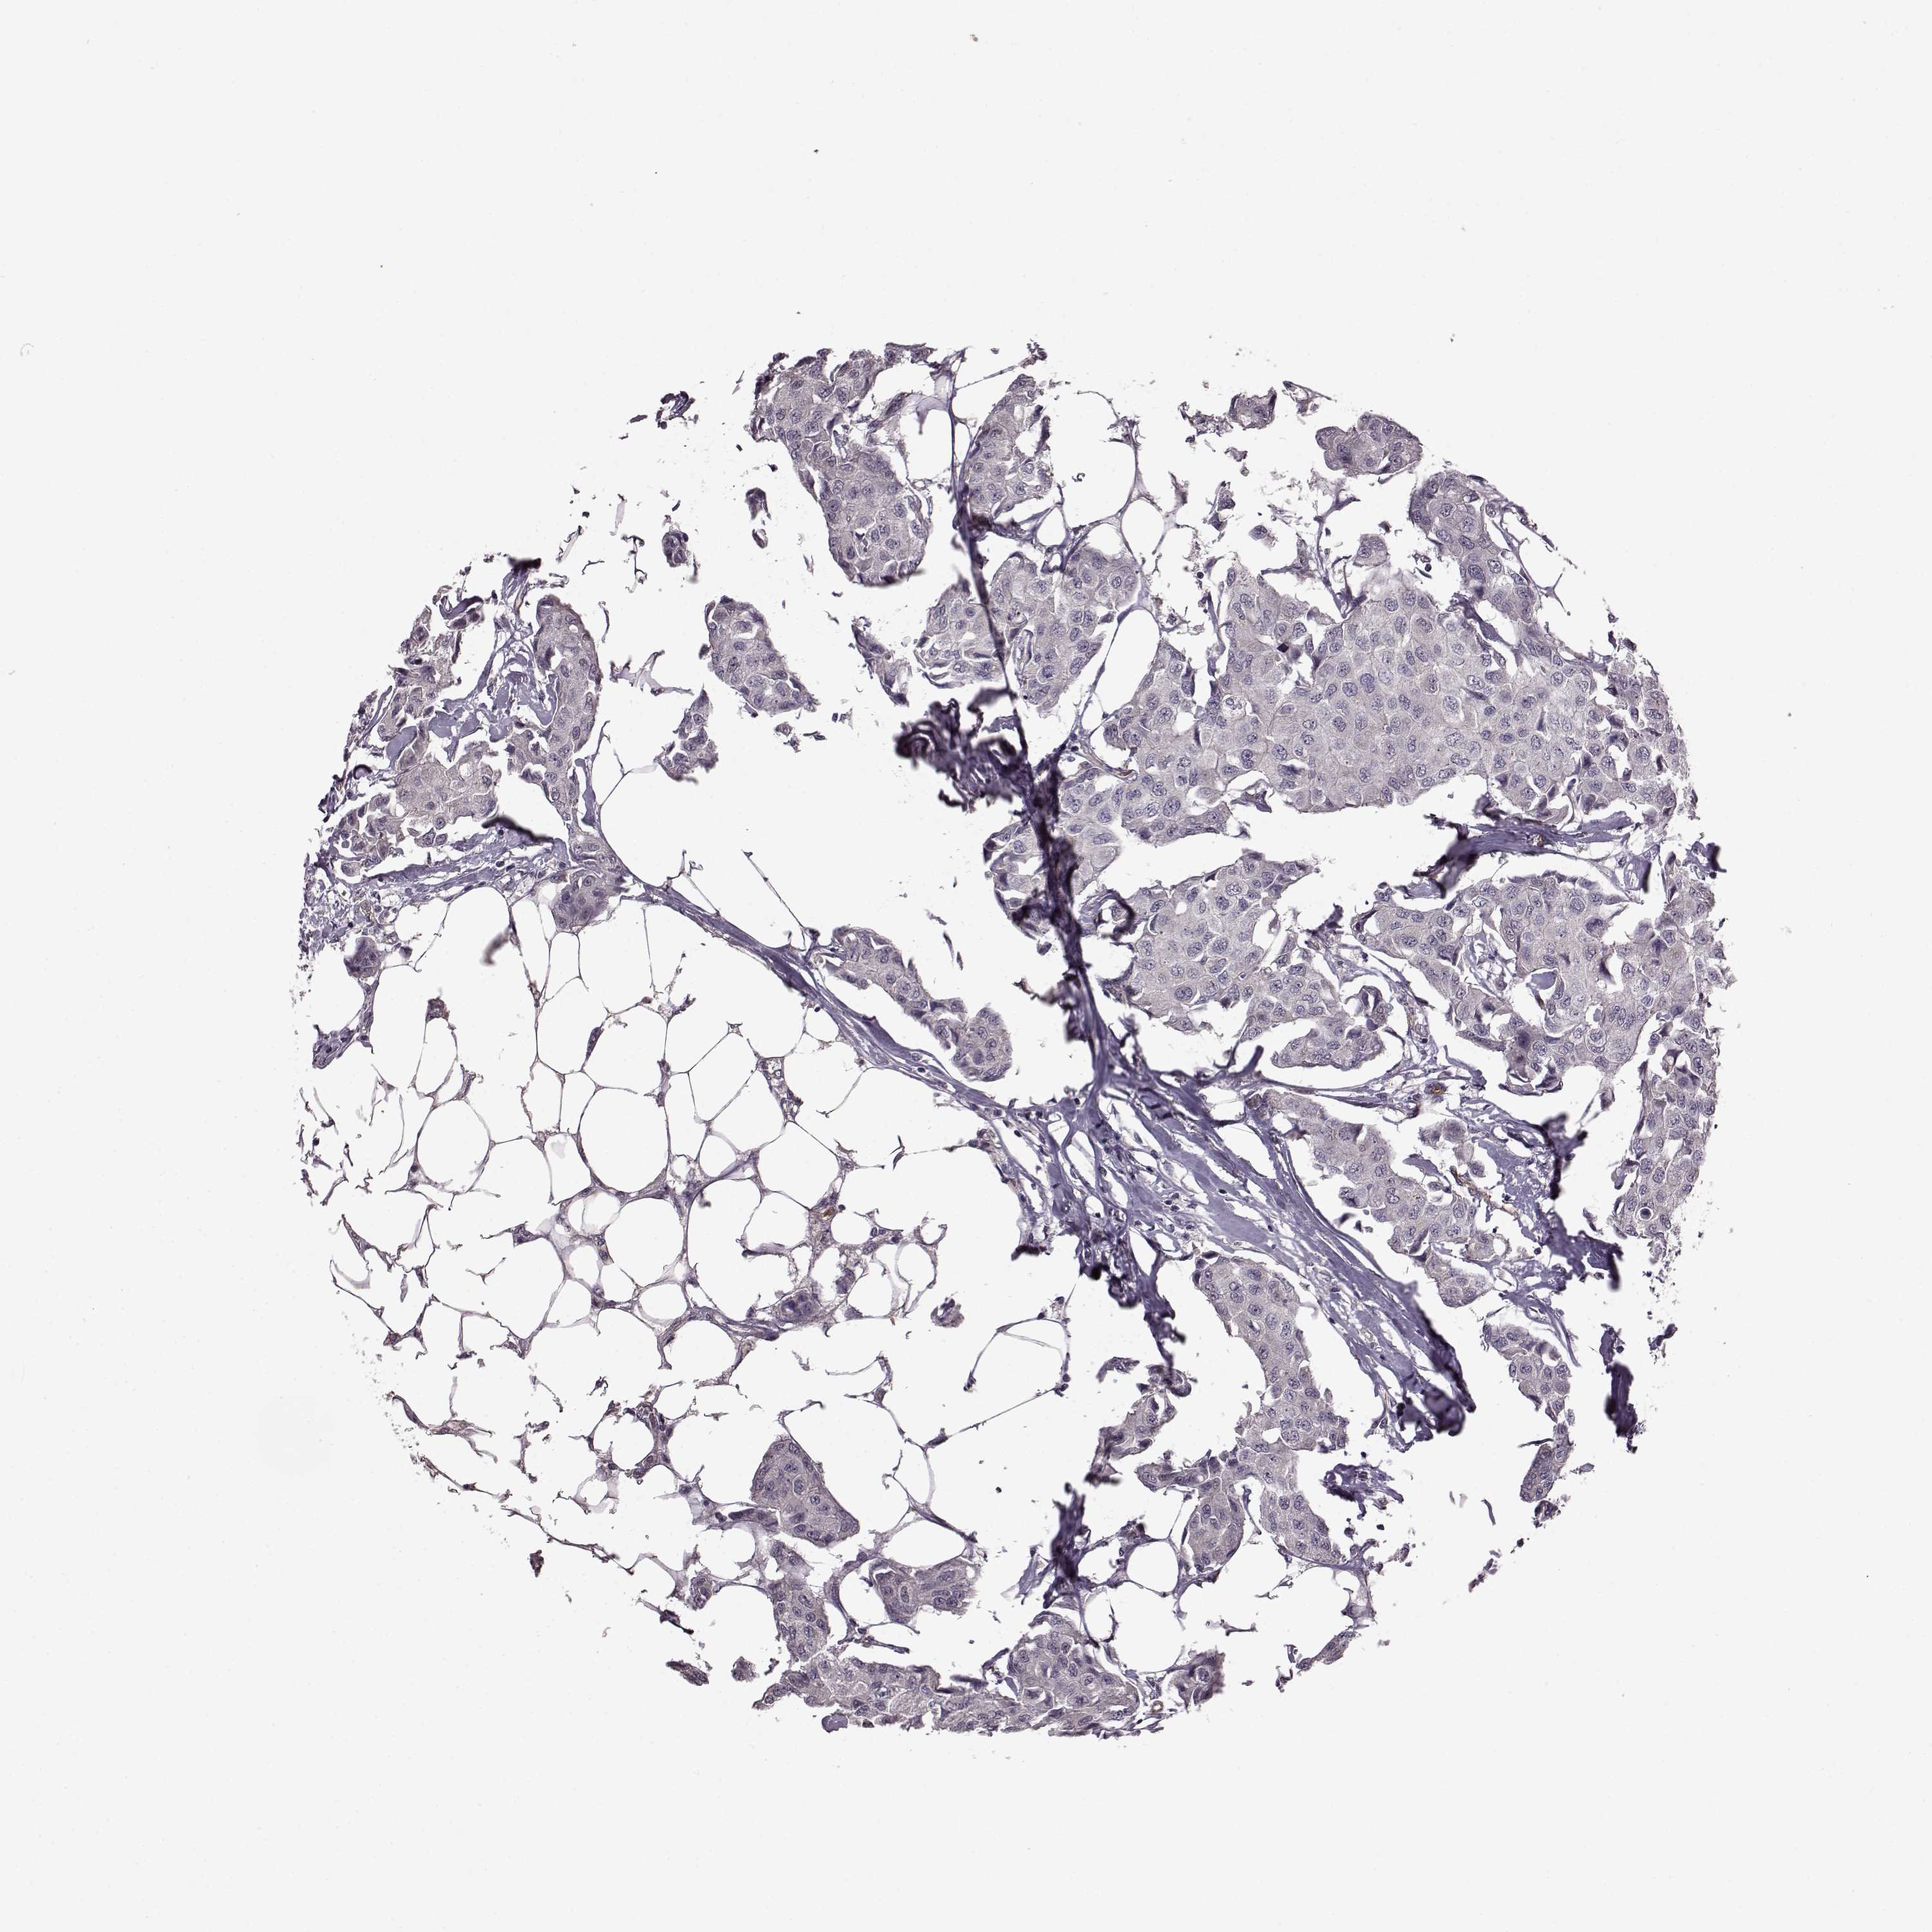

CANCER BREAST CANCER Show tissue menu

BRCA TCGA BRCA VALIDATION PROTEIN EXPRESSION